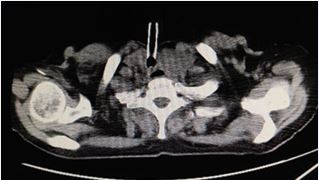

Examination: Physical examination revealed a protruding anterior neck mass with ill-defined borders, mobile upon swallowing. Subcutaneous edema was noted in the left submandibular region Neck ultrasound revealed diffuse thyroid enlargement compressing the trachea, esophagus, and left common carotid artery. CT confirmed a large left thyroid lobe mass, suspected malignancy, with tracheal compression and left jugular vein involvement (Figure 1). Thyroid function tests showed elevated thyroxine (175.6 nmol/L), suppressed TSH (0.12 mU/L), and elevated anti-thyroglobulin (62.3 IU/mL) and anti-TPO antibodies (217.7 IU/mL).

Figure 1 The lesion invades and compresses the trachea, resulting in luminal stenosis, and extends through the membranous portion into the tracheal lumen, partially obstructing the airway (yellow arrow). The left common carotid artery is completely encased by the tumor (red arrow), while the left internal jugular vein is infiltrated with luminal compression and stenosis (blue arrow).